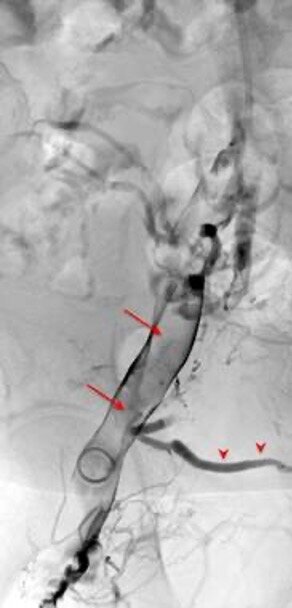

Bei einer interventionellen Behandlung der Beckenvenenthrombose ist kein chirurgischer Schnitt erforderlich. Nach einer örtlichen Betäubung wird durch die Haut in der Kniekehle oder Leistenregion ein Gefäß mit einer Nadel punktiert und ein Katheter eingeführt. Mithilfe von bildgesteuerten Verfahren kann das betroffene Blutgefäß wieder eröffnet werden. Spezielle flexible Stents halten die Engstelle offen. So werden ehemals verschlossene Gefäßäste im Bereich des Beckens offengehalten und der Blutstrom wiederhergestellt.